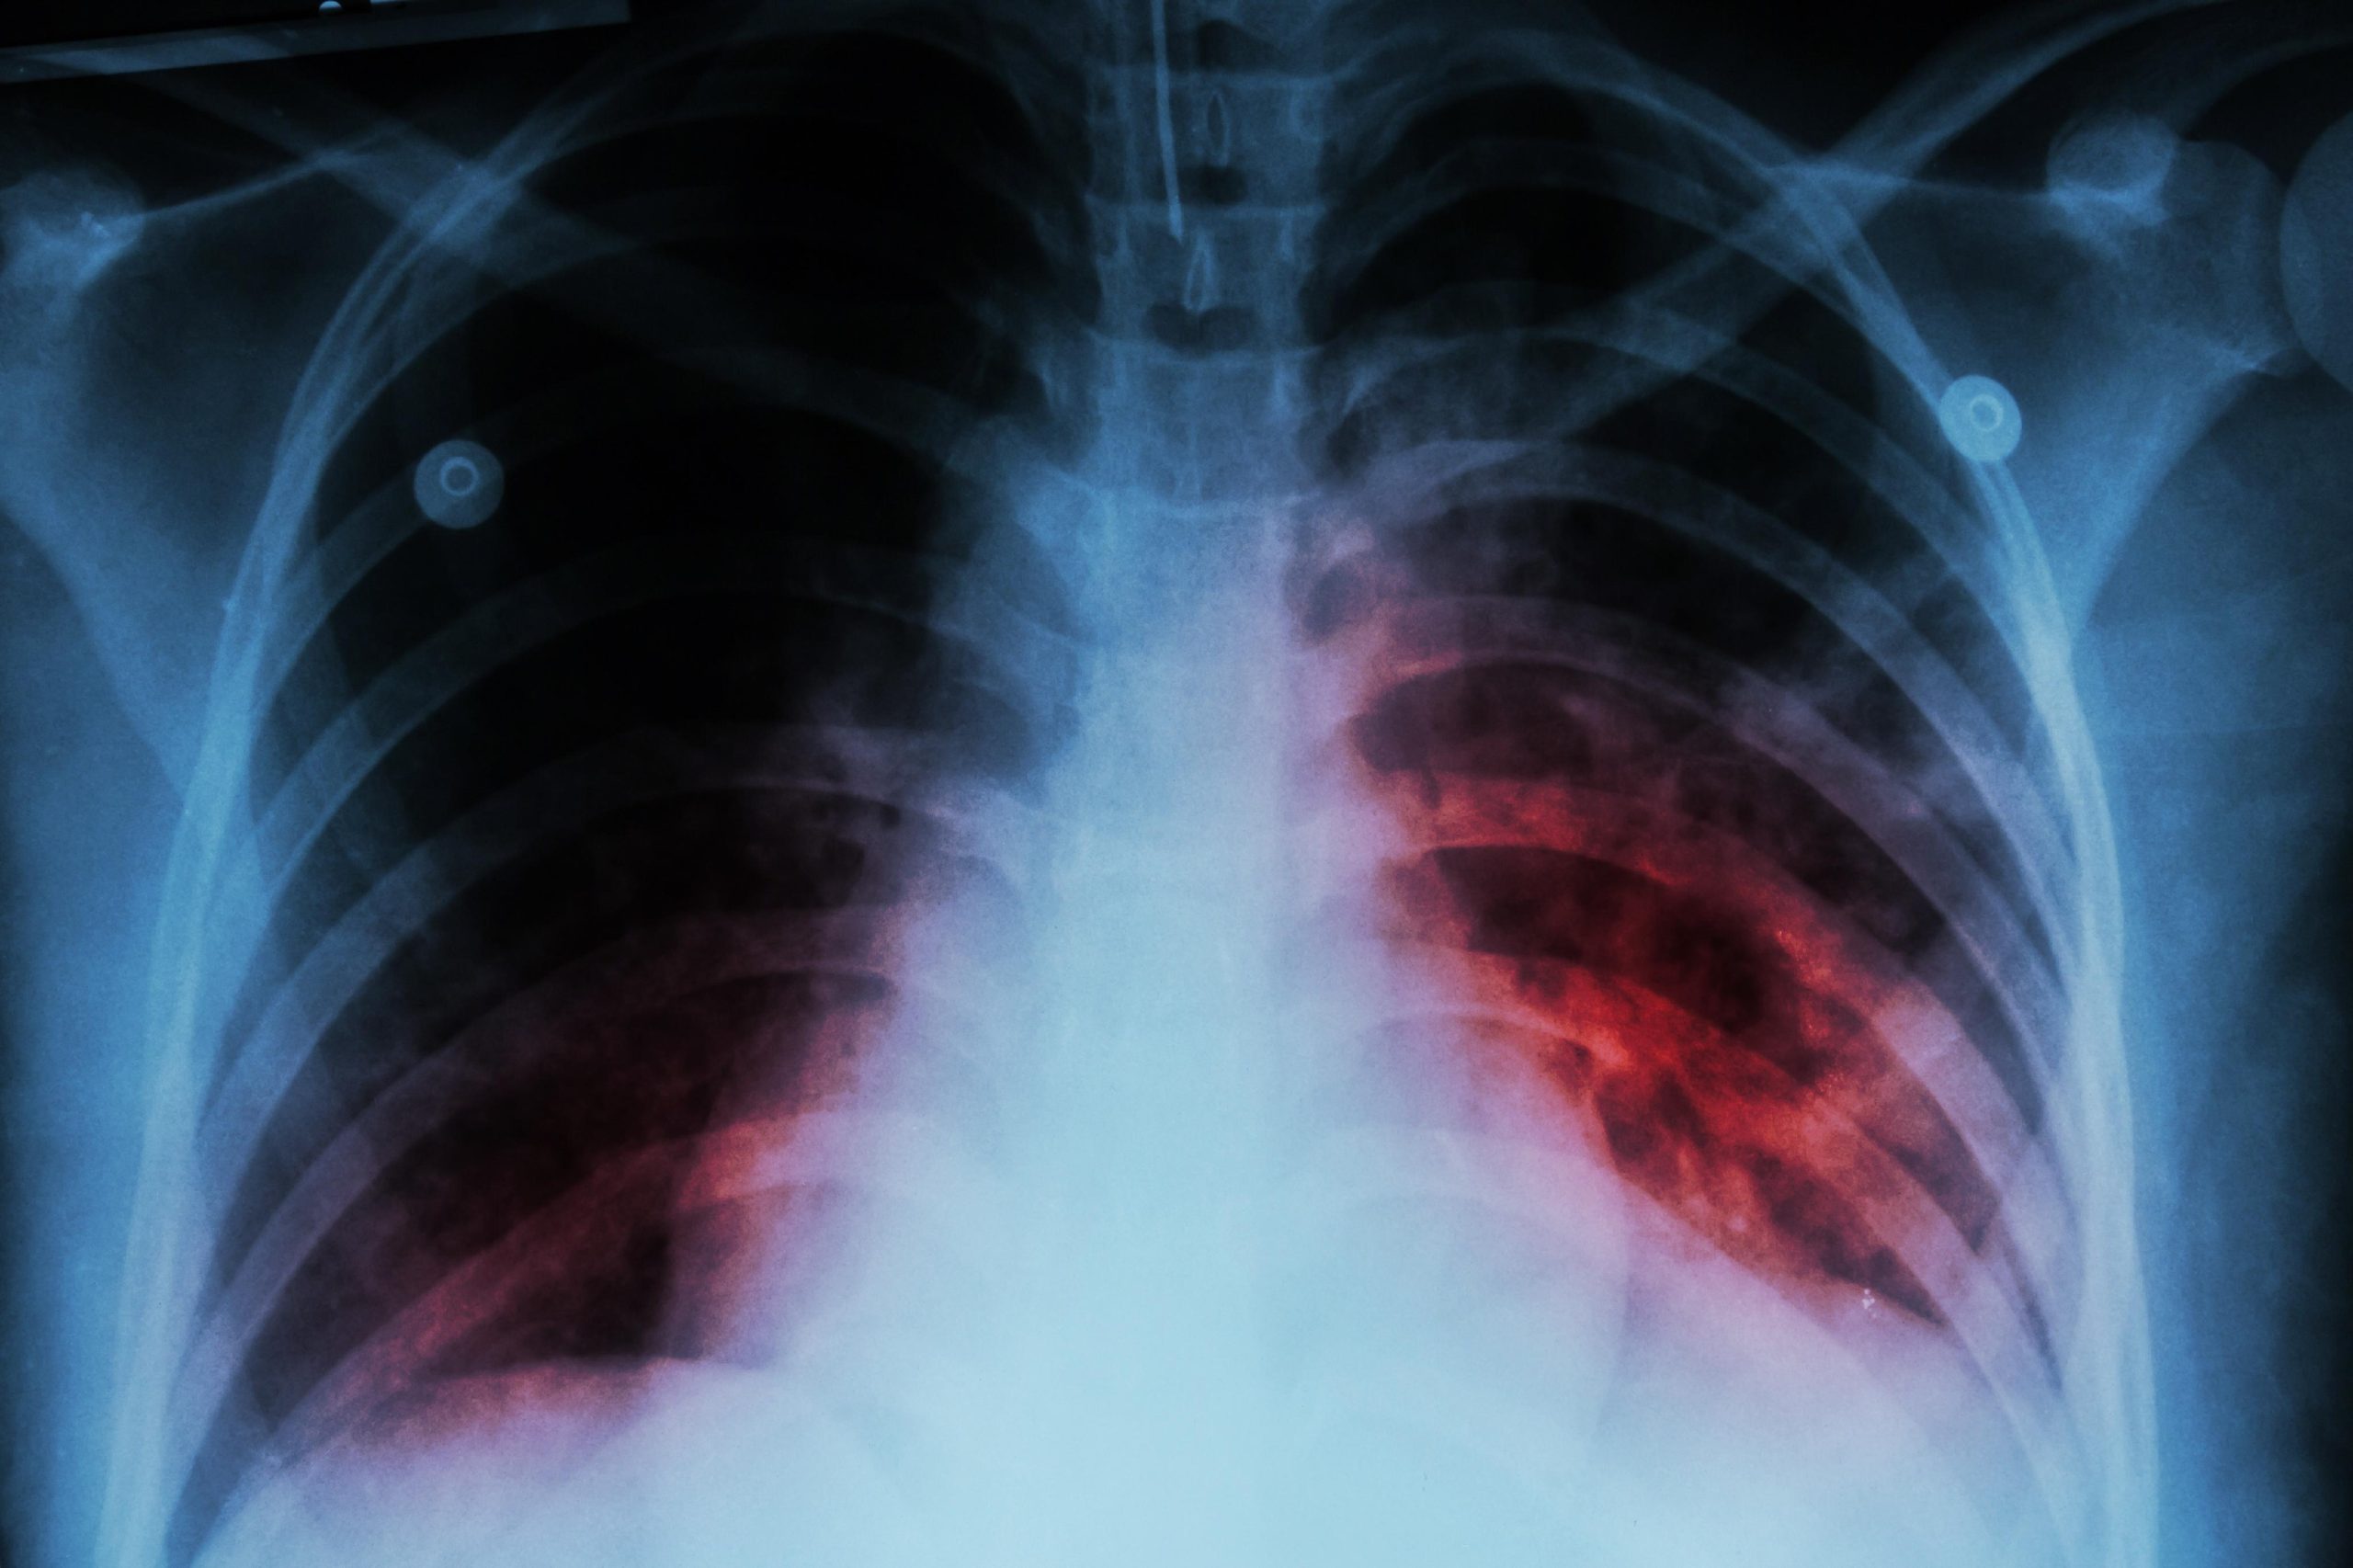

Tuberculosis, commonly known as TB, is a bacterial infection that primarily affects the lungs. It is caused by the bacterium Mycobacterium tuberculosis. TB can also affect other parts of the body such as the brain, kidneys, or spine, although this is less common.TB spreads through the air when an infected person coughs, sneezes, or speaks. It is a highly contagious disease and can be easily transmitted from person to person and can cause a range of symptoms including coughing, fever, fatigue, weight loss, night sweats, and chest pain.